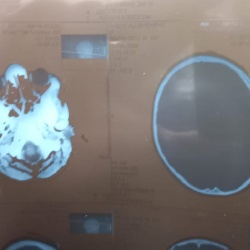

تمكّن فريق طبي متخصص في مدينة الصدر الطبية بالنجف، من إنقاذ طفل يبلغ من العمر 12 عاماً، تعرض لإصابة شديدة نتيجة سقوطه من مكان مرتفع٬ أدت إلى كسر منخسف في الجمجمة مع تضرر أغشية السحايا. وقال أخصائي جراحة الجملة العصبية بالمستشفى، زيد عذاب الزبيدي، في تصريح امس ان (الطفل أُدخل إلى الطوارئ الجراحية وهو في حالة وعي مشوش، حيث تم إجراء الفحوصات اللازمة بما فيها مفراس الدماغ، ليتم بعدها إدخاله بشكل عاجل إلى صالة عمليات الطوارئ).

وأضاف الزبيدي ان (الفريق الجراحي أجرى عملية فوق الكبرى، تم خلالها فتح الجمجمة ورفع الكسر المنخسف الضاغط على الدماغ إلى جانب إصلاح أغشية السحايا الممزقة نتيجة الإصابة٬ وقد تكللت العملية بالنجاح إذ استعاد الطفل وعيه بالكامل بعد خمس ساعات فقط من انتهاء العملية)، وتابع الاخصائي ان (الطفل نُقل لاحقاً إلى ردهة جراحة الجملة العصبية في الطابق الثاني لإكمال العلاج، بعد استقرار حالته الصحية، وغادر المستشفى بعد سبعة أيام وهو بحالة جيدة)، معرباً عن (شكره وتقديره لكادر عمليات الطوارئ الجراحية من أطباء الجراحة والتخدير والفرق التمريضية، كما ثمّن جهودها لدورها بإنجاح العمليات الجراحية في المستشفى). ونجح فريق طبي متخصص في مستشفى الحكيم العام التابع لدائرة صحة النجف، بإنقاذ حياة شاب يبلغ من العمر 30 عاماً ، تعرض لصعقة كهربائية٬ أدت إلى توقف القلب. وأوضح إعلام  المستشفى في بيان تلقته (الزمان) امس ان (المريض وصل إلى قسم الطوارئ وهو فاقد الوعي٬ دون مؤشرات حيوية، ما استدعى تفعيل الإنعاش القلبي الرئوي المتقدم بشكل فوري له)٬ لافتاً الى ان (الملاكات الطبية باشرت بتنفيذ الإجراءات الفورية اللازمة ، وفق السياقات المعتمدة لأجل إنقاذ الشاب)٬ وأضاف ان (التدخل السريع أسفر عن إستعادة الدورة الدموية التلقائية، واستقرار الحالة الصحية للمريض، ثم تم نقله إلى وحدة العناية المركزة٬ لتقديم الرعاية الطبية اللازمة تحت اشراف الفريق الطبي في المستشفى). وانقذ المستشفى٬ طفلة تعاني من نزيف حاد في جدار الصدر٬ اذ استطاع فريق طبي متخصص٬ إنقاذ حياة طفلة تبلغ من العمر أربع سنوات، بعد تعرضها لنزيف حاد داخل جدار الصدر نتيجة مضاعفات معقدة لعملية قلب سابقة أُجريت لها في الخارج. وبينت إدارة المستشفى في تصريح امس ان (الطفلة تعاني من تشوه ولادي معقد في القلب، حيث استقبلها المستشفى بحالة حرجة ترافقها التهابات وخراج، مع انخفاض نسبة الأوكسجين في الدم إلى 60 بالمئة، مع نزف داخلي)٬ موضحاً انه (بعد إجراء الفحوصات الطبية، تقرر إجراء تدخل جراحي عاجل)٬ واكد المستشفى ان (العملية تكللت بالنجاح٬ بجهود الفريق الطبي والتمريضي الساند).